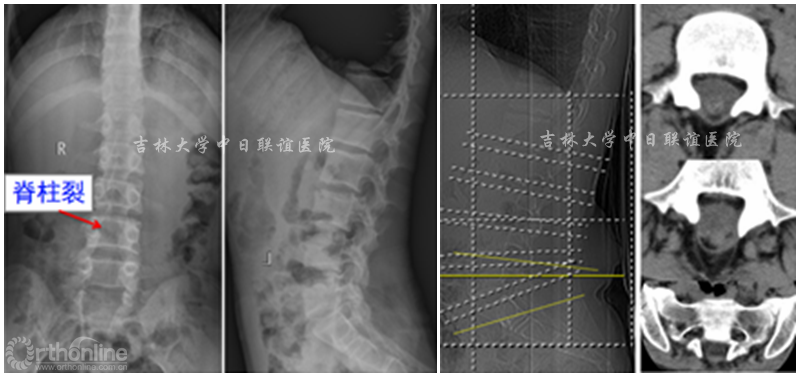

X线:L4—S5 脊柱裂。CT检查:L4-S5棘突及椎板缺失。腰椎MRI示:腰4-骶5椎板缺如,相应椎管内结构紊乱,脊髓末端与椎管内组织粘连固定于腰4椎体下缘,脊膜向外膨出,考虑脊柱裂伴脊膜膨出及脊髓栓系。

术前影像学检查: